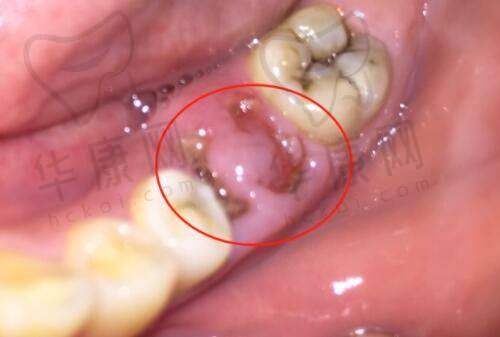

众多在合肥艺星医疗美容医院找朱继锋医生做鼻部整形的顾客都取得了满意的成效。有一位顾客原本是塌鼻梁,鼻头也比较圆润,缺乏立体感。朱继锋医生根据她的面部特征和个人需求,为她制定了鼻综合整形方案,采用了自体肋软骨隆鼻和鼻尖塑形等技术。术后,顾客的鼻子变得高挺立体,与面部其他五官更加协调,整个人的魅力也得到了较大的提升。而且修复过程中,由于朱继锋医生手术创伤小,顾客的修复时间也相对较短,特别快就能够正常生活和工作。

还有一位顾客之前做过隆鼻手术,但出现了假体移位的问题,找到朱继锋医生进行修复。朱继锋医生凭借自己丰富的经验和不错的技术,成功地为顾客修复了鼻子,使鼻子修复了自然美观的状态,顾客对修复成效非常满意。